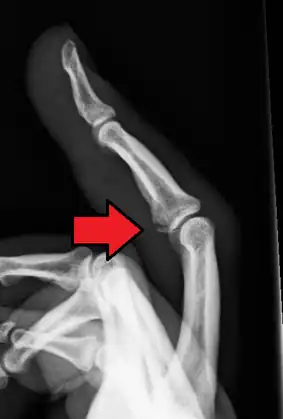

Avulsion fracture of a fingertip bone

An avulsion fracture is a bone fracture which occurs when a fragment of bone tears away from the main mass of bone as a result of physical trauma. This can occur at the ligament by the application of forces external to the body (such as a fall or pull) or at the tendon by a muscular contraction that is stronger than the forces holding the bone together. Generally muscular avulsion is prevented by the neurological limitations placed on muscle contractions. Highly trained athletes can overcome this neurological inhibition of strength and produce a much greater force output capable of breaking or avulsing a bone.